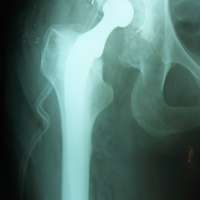

Case:3 Septic Arthritis-THR

Imm Post-Op

Total Hip Replacement